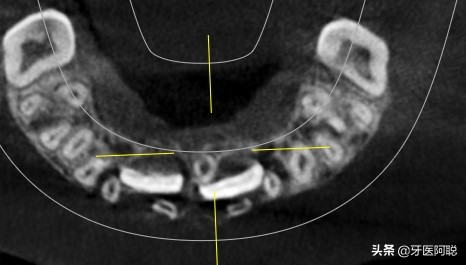

在孩子还是一个胚胎的时候,会形成32颗恒牙蕾。但如果在恒牙形成的过程中孩子的牙板增殖剧烈,会形成超过正常数量的牙齿。在孩子出生以后成长的过程中,这个多余的牙齿也会长出来,就会形成多生牙。这样的牙齿,一般是在门牙处比较常见。